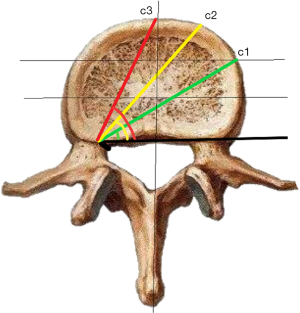

c1: the angle between the projection, which is generated from the posterior corner of the upper vertebral body to contralateral front-middle 1/3 on the endplate, and the tangent line to the posterior border of the vertebral body.

c2: the angle between the projection, which is generated from the posterior corner of the upper vertebral body to contralateral anterior corner on the endplate, and the tangent line to the posterior border of the vertebral body.

c3: the angle between the projection, which is generated from the posterior corner of the upper vertebral body to the midpoint of the anterior border on the endplate, and the tangent line to the posterior border of the vertebral body.

The angles of oblique fixation from posterior corner in lumbar spine in sagittal and axial planes (Figures 5-9).